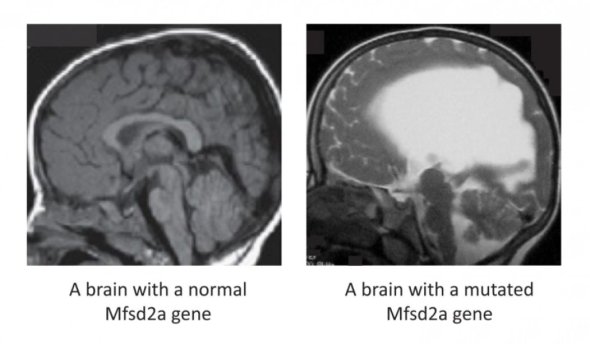

The difference between a brain with a normal Mfsd2a gene and a brain with a mutated Mfsd2a gene.

New research has proved that certain special fats found in blood are essential for human brain growth and function. The two studies showed that mutations in the protein Mfsd2a causes impaired brain development in humans. Mfsd2a is the transporter in the brain for a special type of fat called lysophosphatidylcholines (LPCs) — composed of essential fatty acids like omega-3. These studies show, for the first time, the crucial role of these fats in human brain growth and function.